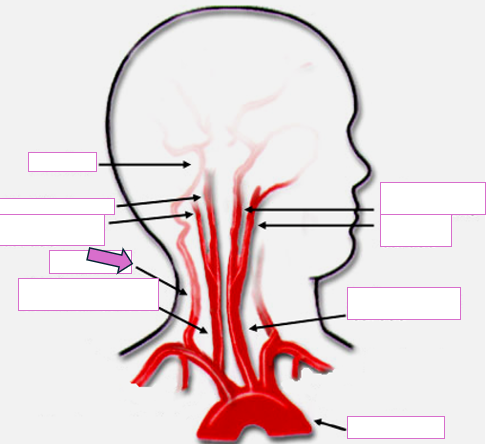

Based on the indicated area, identify this vessel

Brachiocephalic/innominate artery

Right subclavian artery

Right vertebral artery

Right carotid artery

Left carotid artery

Left vertebral artery

Left subclavian artery

Aortic arch